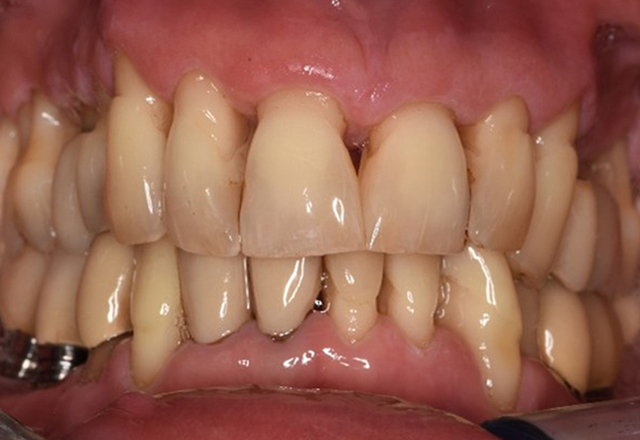

The healthy patient with pre-existing periodontal disease & peri-implantitis

A 52-year-old patient presents at a preventive care session. The patient has no systemic disease and is not taking any medication. He has had various dental treatments and also has two active carious lesions. In addition, the patient has four implants (2nd, 3rd and 4th quadrants). He is revealed to have early periodontal disease (stage IV, grade B). His periodontal condition is stable; a probing depth of Probing depths (ST) of 5 mm is only evident at the implant in region 36. Gingivitis is also identified. more

Pacient sănătos cu boală parodontală incipientă

Pacientul în vârstă de 68 de ani nu are nicio afecțiune generală și nu ia niciun medicament care ar putea fi relevant pentru sănătatea sa orală, iar stilul său de viață nu prezintă niciun risc special. Pacientul are două implanturi dentare (cadranul 3, de cinci ani) și un caz anterior de boală parodontală (stadiul IV, gradul B) cu pierderea dinților. În prezent, condițiile parodontale sunt stabile. Cu toate acestea, parodontoza crește semnificativ complicațiile biologice ale implanturilor și există riscul de pierdere a implanturilor (21). Se pot determina patru recomandări pentru ședința de profilaxie. mai multe